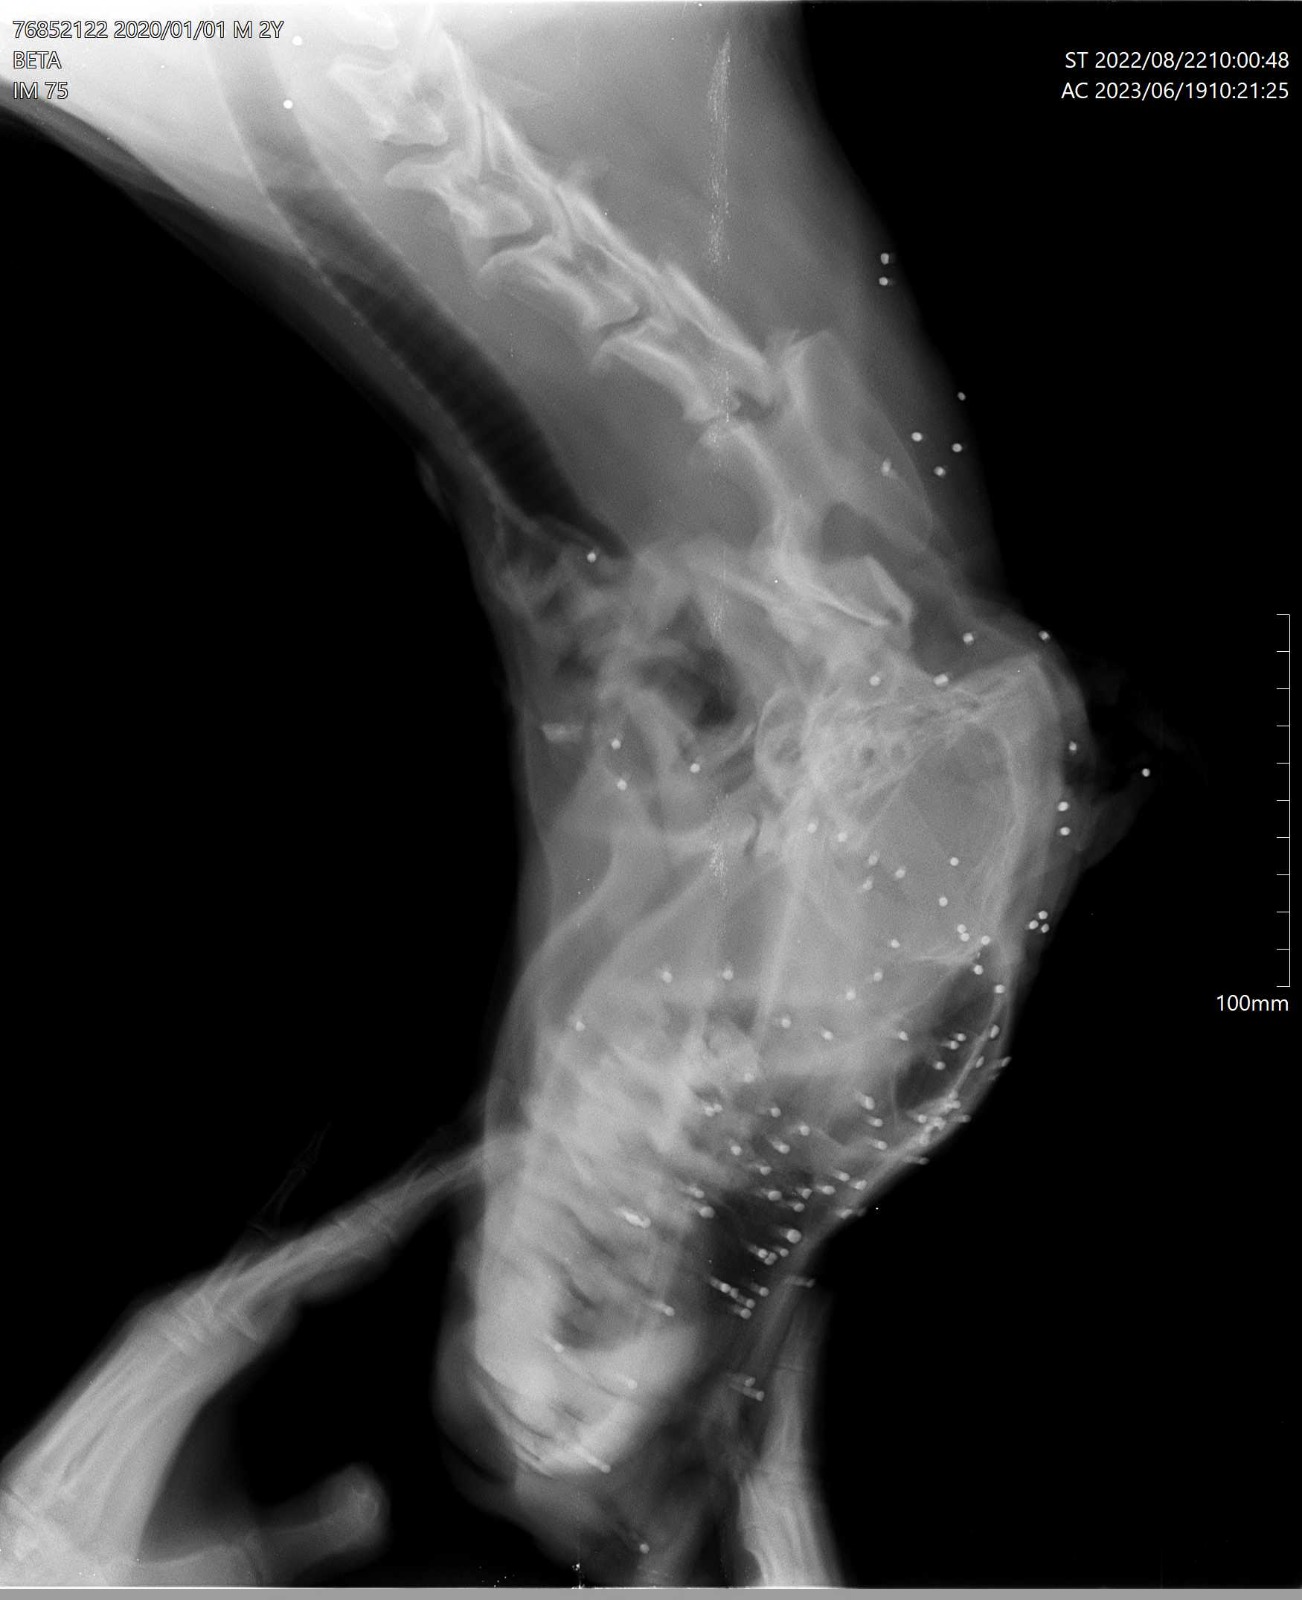

His blood tests came back positive for ehrlichia as well as leshmenia, his xrays show that pellets were behind his blindness which sadly means, yet another victim of a shooting has entered our shelter and to top it all off he was deemed medically emaciated !